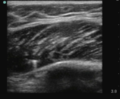

Abscess

Novice sonographers can predict a positive I&D with SN 0.97 and SP 0.67 (vs clinical exam 0.76 and 0.83)[1]

Images

- Positive scan (not all elements are required to make a diagnosis)

- Fluid collect seen has heteroechoic or hypoechoic circular area

- Hyperechoic ring

- Posterior acoustic enhancement

- Swirling or Squish Sign (movement of abscess debris) with compression